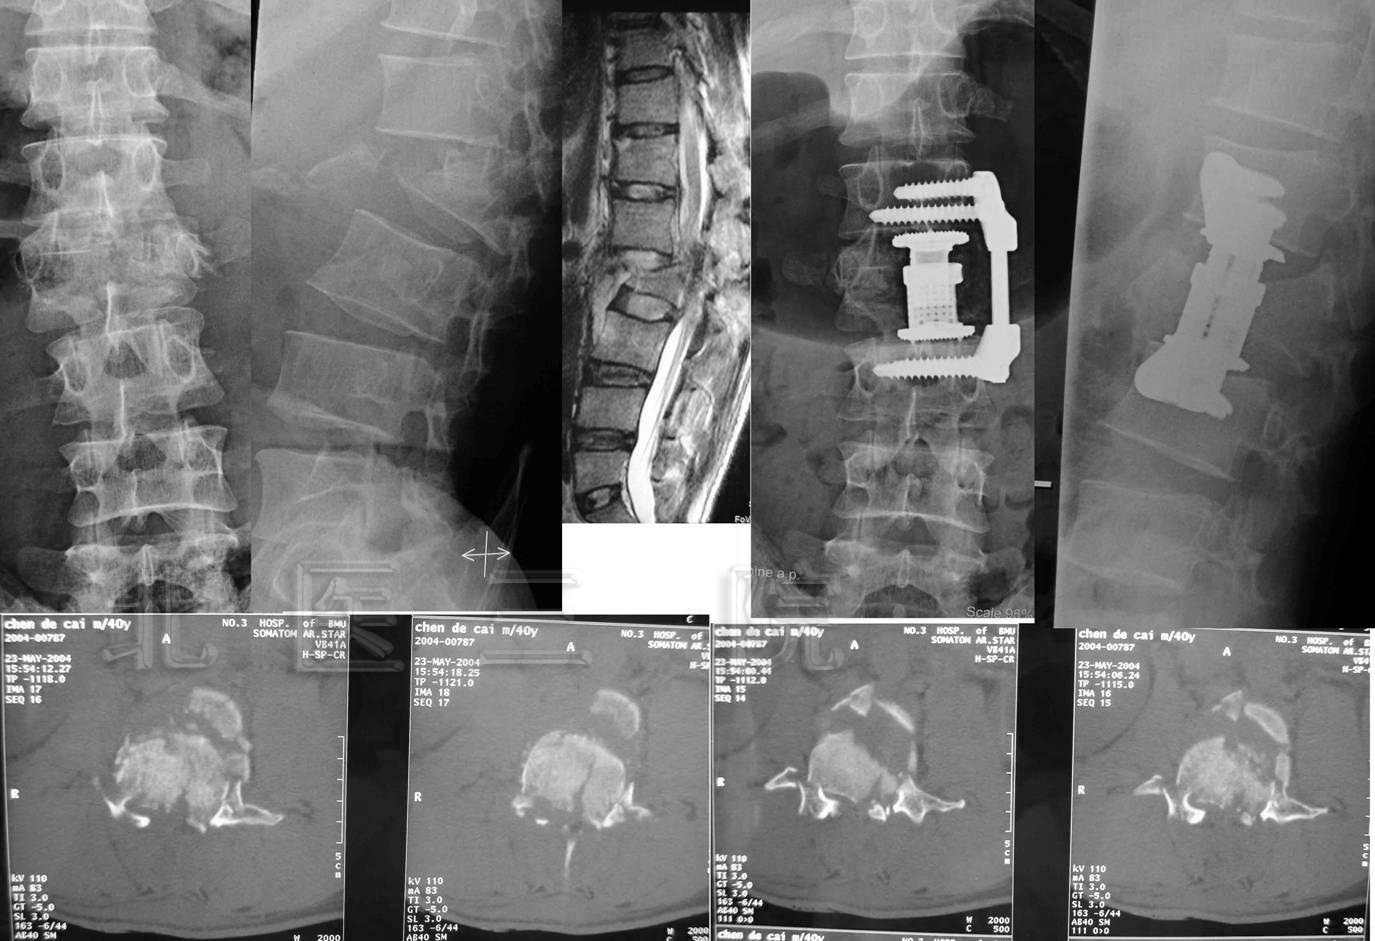

9岁男孩重物砸伤腰部导致L4-5骨折脱位,行L4-5骨折脱位减压复位+L3-S1椎弓根固定术,术后3个月患者复查可扶拐行走。

A 9-year-boy who had L4-5 fracture and dislocation resulted from heavy goods drop on the back Decompression, reduction of L4-5 fracture and dislocation , L3-S1 pedicle screw fixation.were performed. Three months later he could walk with crutches.

11.L3爆散性骨折脱位

男,38岁,L3爆散性骨折脱位伴尾神经完全损伤3周入院

术后可乘坐轮椅